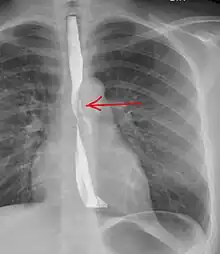

Upright chest radiography showing mediastinal air adjacent to the aorta and tracking cephalad adjacent to the left common carotid artery. This patient presented to the Emergency department with severe chest pain after eating.

Upright chest radiography showing mediastinal air adjacent to the aorta and tracking cephalad adjacent to the left common carotid artery. This patient presented to the Emergency department with severe chest pain after eating. Sagittal remormatted CT image showing discontinutity in the wall of the posterolateral aspect of the distal esophagus